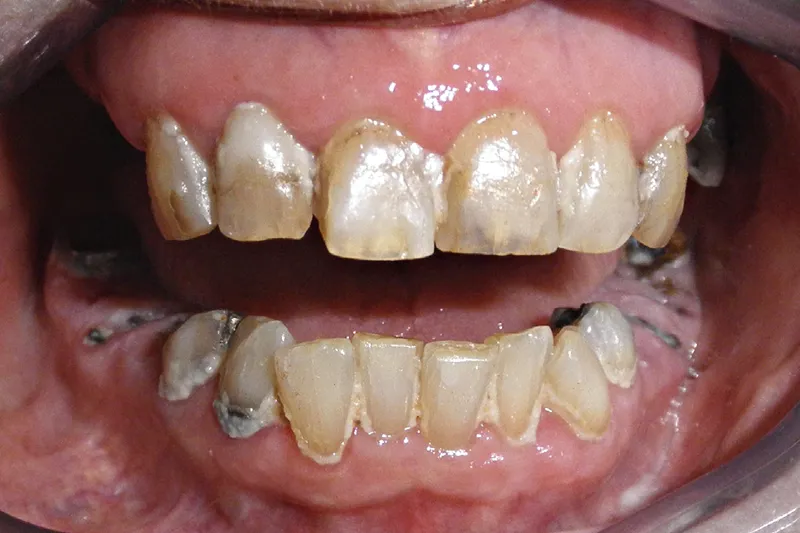

Baggrund – Mange skrøbelige ældre har dårlige tandsæt; stærkt destruerede tænder, som ikke kan restaureres, og rodrester med åbne rodkanaler ses hyppigt i kombination med periapikal og parodontal inflammation. Der ligger en stor udfordring for tandplejen i at forbedre den orale status for den voksende gruppe af skrøbelige ældre med egne tænder. Tandlæger er ofte usikre på, hvordan de skal håndtere rodrester og destruerede tænder uden mulighed for restaurering på skrøbelige ældre patienter.

Background – Many frail older adults have an unhealthy dentition; unrestorable broken teeth and root remnants with open root canals, commonly accompanied by periapical and periodontal inflammation, are often seen. Improving oral health in the growing group of frail older adults with remaining teeth is a considerable challenge for dental care professionals. Dentists are often un- certain how to deal with root remnants and unrestorable broken teeth in frail older adults.